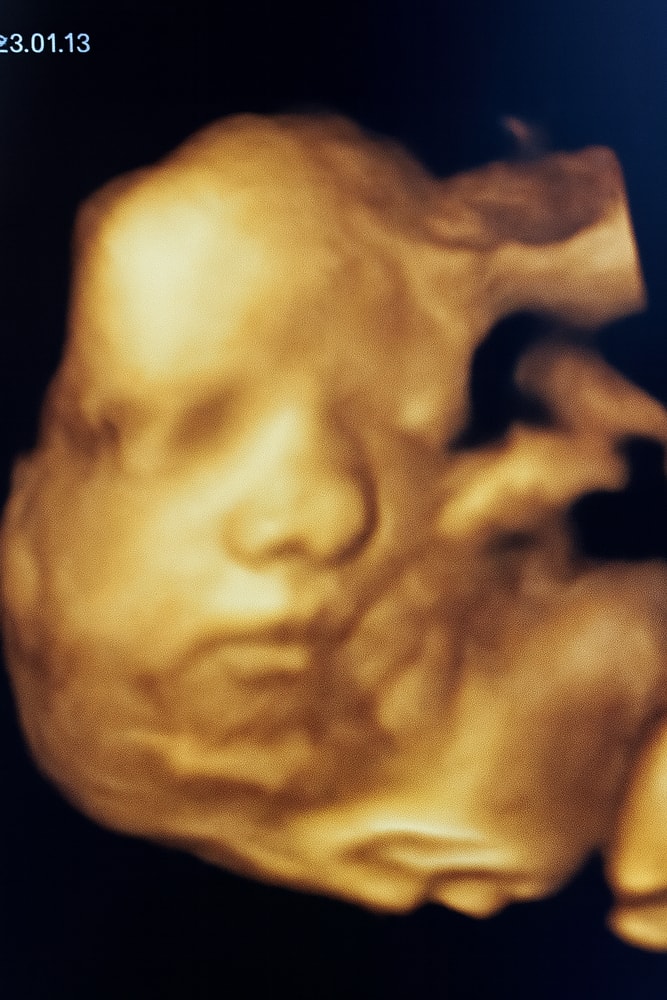

33 недельки моей булочки🥰

Всё о нашей беременностиНа прошлой недельки был очередной контроль, все славу Богу тьфу тьфу тьфу идем по всем меркам хорошо и по параметрам☺️

вес малышки -2172 гр

ручки, ножки, головка животик все идут по срокам +-2,3 дня опережает

ну и мы уже приняли положение головкой☺️вниз🙏